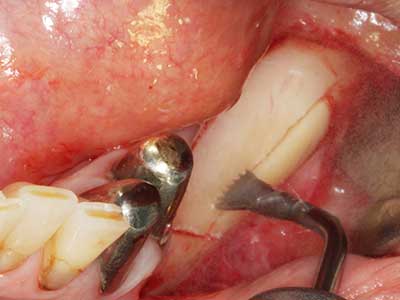

Bone tissue is not simply a mineral structure but also contains a substantial proportion of collagen fibres. This means it not only has good compressive strength but also a degree of flexibility, which can be taken advantage of when performing bone augmentations. In the classical expansion procedure using bone splitting, the atrophied alveolar ridge is split longitudinally and carefully expanded after reaching an adequate osteotomy depth (Fig. 13-16), ideally without substantial removal of the periosteum (Brugnami, Caiazzo et al. 2014, Stricker, Fleiner et al. 2014). Screw and plate systems with increasing expansion distance have proven effective in separating the two bone lamellae while remaining below the fracture threshold. In general, residual bone widths of at least 3–4 mm are required (Chiapasco, Zaniboni et al. 2006) to guarantee adequate flexibility and sufficient bone coverage of the future implants. If necessary, a vertical relief osteotomy on one or both sides can improve flexibility. A combination with additional augmentation techniques, particularly on the buccal side, has been described as an alternative to the classical technique.

The splitting procedure is particularly atraumatic and there is no significant loss of dimension when using piezosaws, and there are no significant differences between implants in split jaws and implants in an alveolar ridge without a bone deficit (Chiapasco, Zaniboni et al. 2006, Danza, Guidi et al. 2009). However, sufficient continuous irrigation is essential, particularly with locally restricted and deep splitting to prevent thermal stress in the apical osteotomy regions.